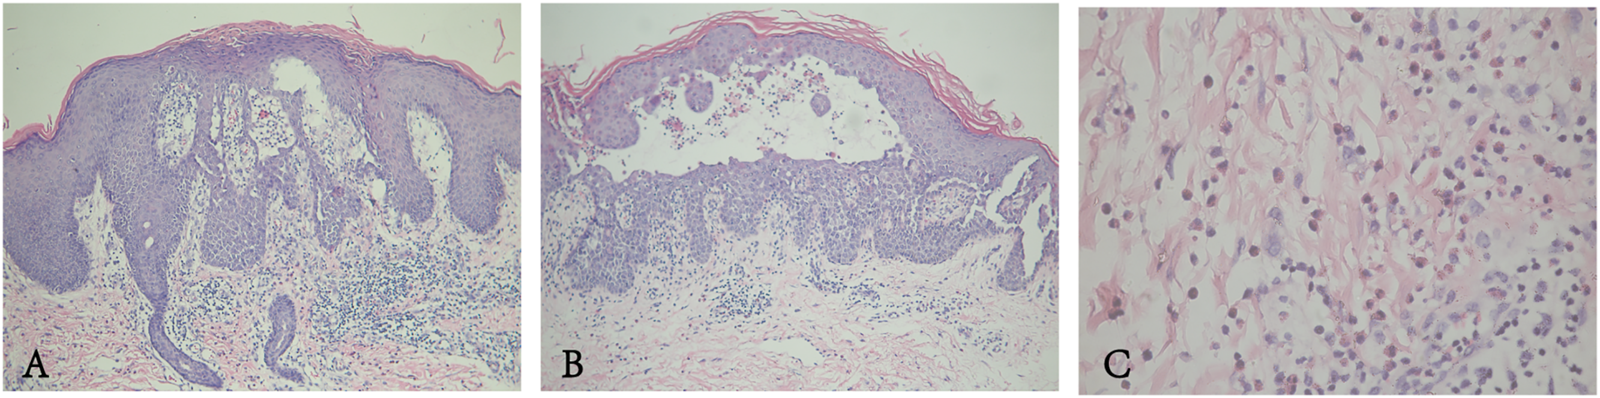

FIGURE 2

(A,B) Epidermal hyperkeratosis accompanied by parakeratosis, acantholysis with the appearance of a dilapidated brick-wall, and formation of intraepidermal blisters. (C) Some lymphocytes and a few eosinophils in the dermis.

The proband was a 24-year-old male, who presented with pruritic skin lesions in his genital and perianal regions for more than 7 years. On physical examination, multiple bright red verrucous papules were observed in his mons pubis, bilateral groins, scrotum, perineum, and crissum (Figures 1A–C). His general health was normal. Mycological examination of scales showed no hyphae and spores under a light microscope. The acetic acid white test was negative. PCR detection of the HPV DNA showed the absence of HPV. All blood TRUST, TPPA, and anti-HIV antibody tests were also negative. Histopathology of a biopsy from his right groin showed epidermal hyperkeratosis, parakeratosis, downward proliferation with a finger-like protrusion, and acantholysis with the appearance of a dilapidated brick-wall as well as the formation of a blister in the epidermis. In addition, there were vascular dilatation in the dermal papilla and infiltration of lymphocytes and eosinophils in the dermis (Figure 2). His mother was a 45-year-old woman, who presented with relapsing flares of mild erythema under her armpits for many years. His father was unaffected. The proband was diagnosed with Hailey–Hailey disease on the basis of his clinical and laboratory findings. He was administered with the treatment of oral cephradine, cleansing of 1:5,000 potassium permanganate solution, and topical 2% mupirocin ointment. The warty papules were dramatically improved after 5 days of his second visit (Figures 1D–F). Oral cetirizine and cyproheptadine were then given to relieve severe itching. Four weeks later, a few greyish white small papules were still present in his bilateral groins (Figures 1G–I). Therefore, the combination of tacalcitol ointment and mucopolysaccharide polysulfate cream was then used.

HHD is one of the acantholytic conditions or papular acantholytic dyskeratosis. The common histopathological findings are the epidermal parakeratosis, dyskeratosis, suprabasal acantholytic cleft or bulla, and the typical appearance of “dilapidated brick-wall.” In general, intercellular deposition of IgG and complement 3 (C3) is not detected in the epidermis of HHD patients in contrast to autoimmune pemphigus. However, one HHD patient had linear deposition of C3 along the dermoepidermal junction (Gu et al., 1999). Anti-desmoglein and anti-desmocollin antibodies are found in sera of two cases of HHD patients (Bennani et al., 2012; Ueo et al., 2015). Moreover, fixed and soluble immune complexes are present in the epidermis of patients (Makhneva and Beletskaya, 2007). Regretfully, we did not perform direct immunofluoresence staining and serum autoantibodies detection for the patient. Probably, the formation of anti-desmoglein antibodies, anti-desmocollin antibodies, and immune complexes is associated with the unmasking of desmosomal antigens due to acantholysis. These conditions suggest that immunological factors are also involved in the pathogenesis of HHD in addition to a genetic defect. The speculation could provide a plausible explanation for the use of corticosteroids or immunosuppressants in HHD. In addition, abnormally elevated oxidative stress levels have been found in the keratinocytes of HHD; a small number of patients with refractory symptoms achieved good efficacy with antioxidant drugs (Biolcati et al., 2014).